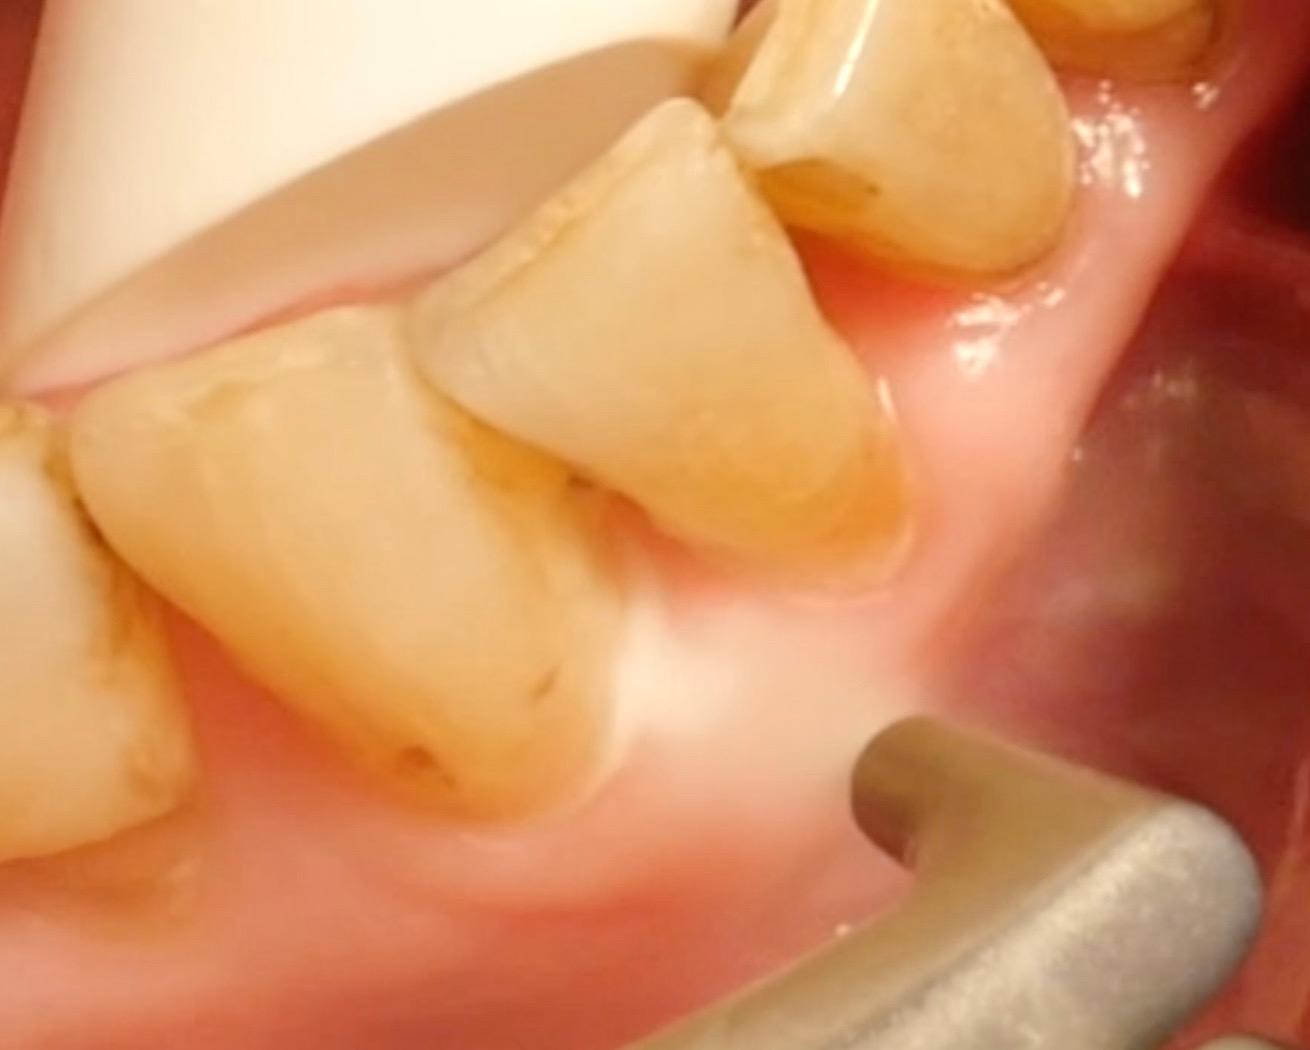

• Supra- and subgingival use of glycine-based powders is safe and effective.

• In contrast, powders containing sodium bicarbonate should not be used in periodontal treatment, because these powders can cause considerable damage to exposed cementum and dentine and to the gums.